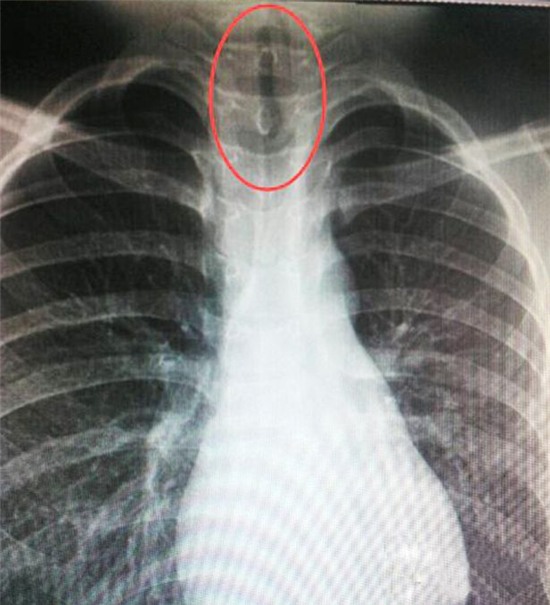

Old  Default Kinh hoàng khi chứng kiến đỉa kẹt trong ống thở.

Cậu bé Xiabo Chien liên tục kêu đau họng và choáng váng. Thật không ngờ đó là hậu quả của việc dừng lại uống nước bên hồ ở vệ đường.

Bà Xiang Tung, 33 tuổi, mẹ của Xiabo cho biết: “Lúc đầu chúng tôi tưởng thằng bé bị cúm vì nó nói nó bị choáng và đau họng. Thằng bé không nói đã dừng lại uống nước ao bên đường nên không ai nghĩ có thể nó đã nuốt phải cái gì đó”.Vì nghĩ con ốm xoàng, gia đình cho Xiabo uống thuốc rồi để cậu nghỉ ngơi. Nhưng tình hình mỗi lúc một tệ hơn nên cậu bé được đưa đến bệnh viện.Tại đây cậu bé 11 tuổi được đưa đi chụp X-quang và kết quả phim chụp khiến nhiều người hoảng hốt: Một con đỉa cỡ 7cm bị mắc kẹt ở cổ họng.

Đại diện bệnh viện cho biết: “Chúng tôi phát hiện ra rằng cậu bé đã nuốt phải ấu trùng đỉa. Có thể ấu trùng đã tìm cách đi lên được phía cổ họng để lấy không khí, nó cứ thế “lớn dần” tới 7 cm. Mỗi khi con đỉa ngọ nguậy sẽ làm kẹt đường thở và khiến cậu bé không còn tỉnh táo.

Thật may là chưa nhiễm trùng. Các bác sĩ có thể lấy con đỉa ra không mấy phức tạp. Xiabo sau đó đã cảm thấy khá hơn.

Hồ nước mà Xiabo đã uống bên đường được nông dân tự đào để lấy nước tưới cho những cánh đồng của họ ở hạt Huidong, nằm về phía tây nam tỉnh Sichuan, Trung Quốc.